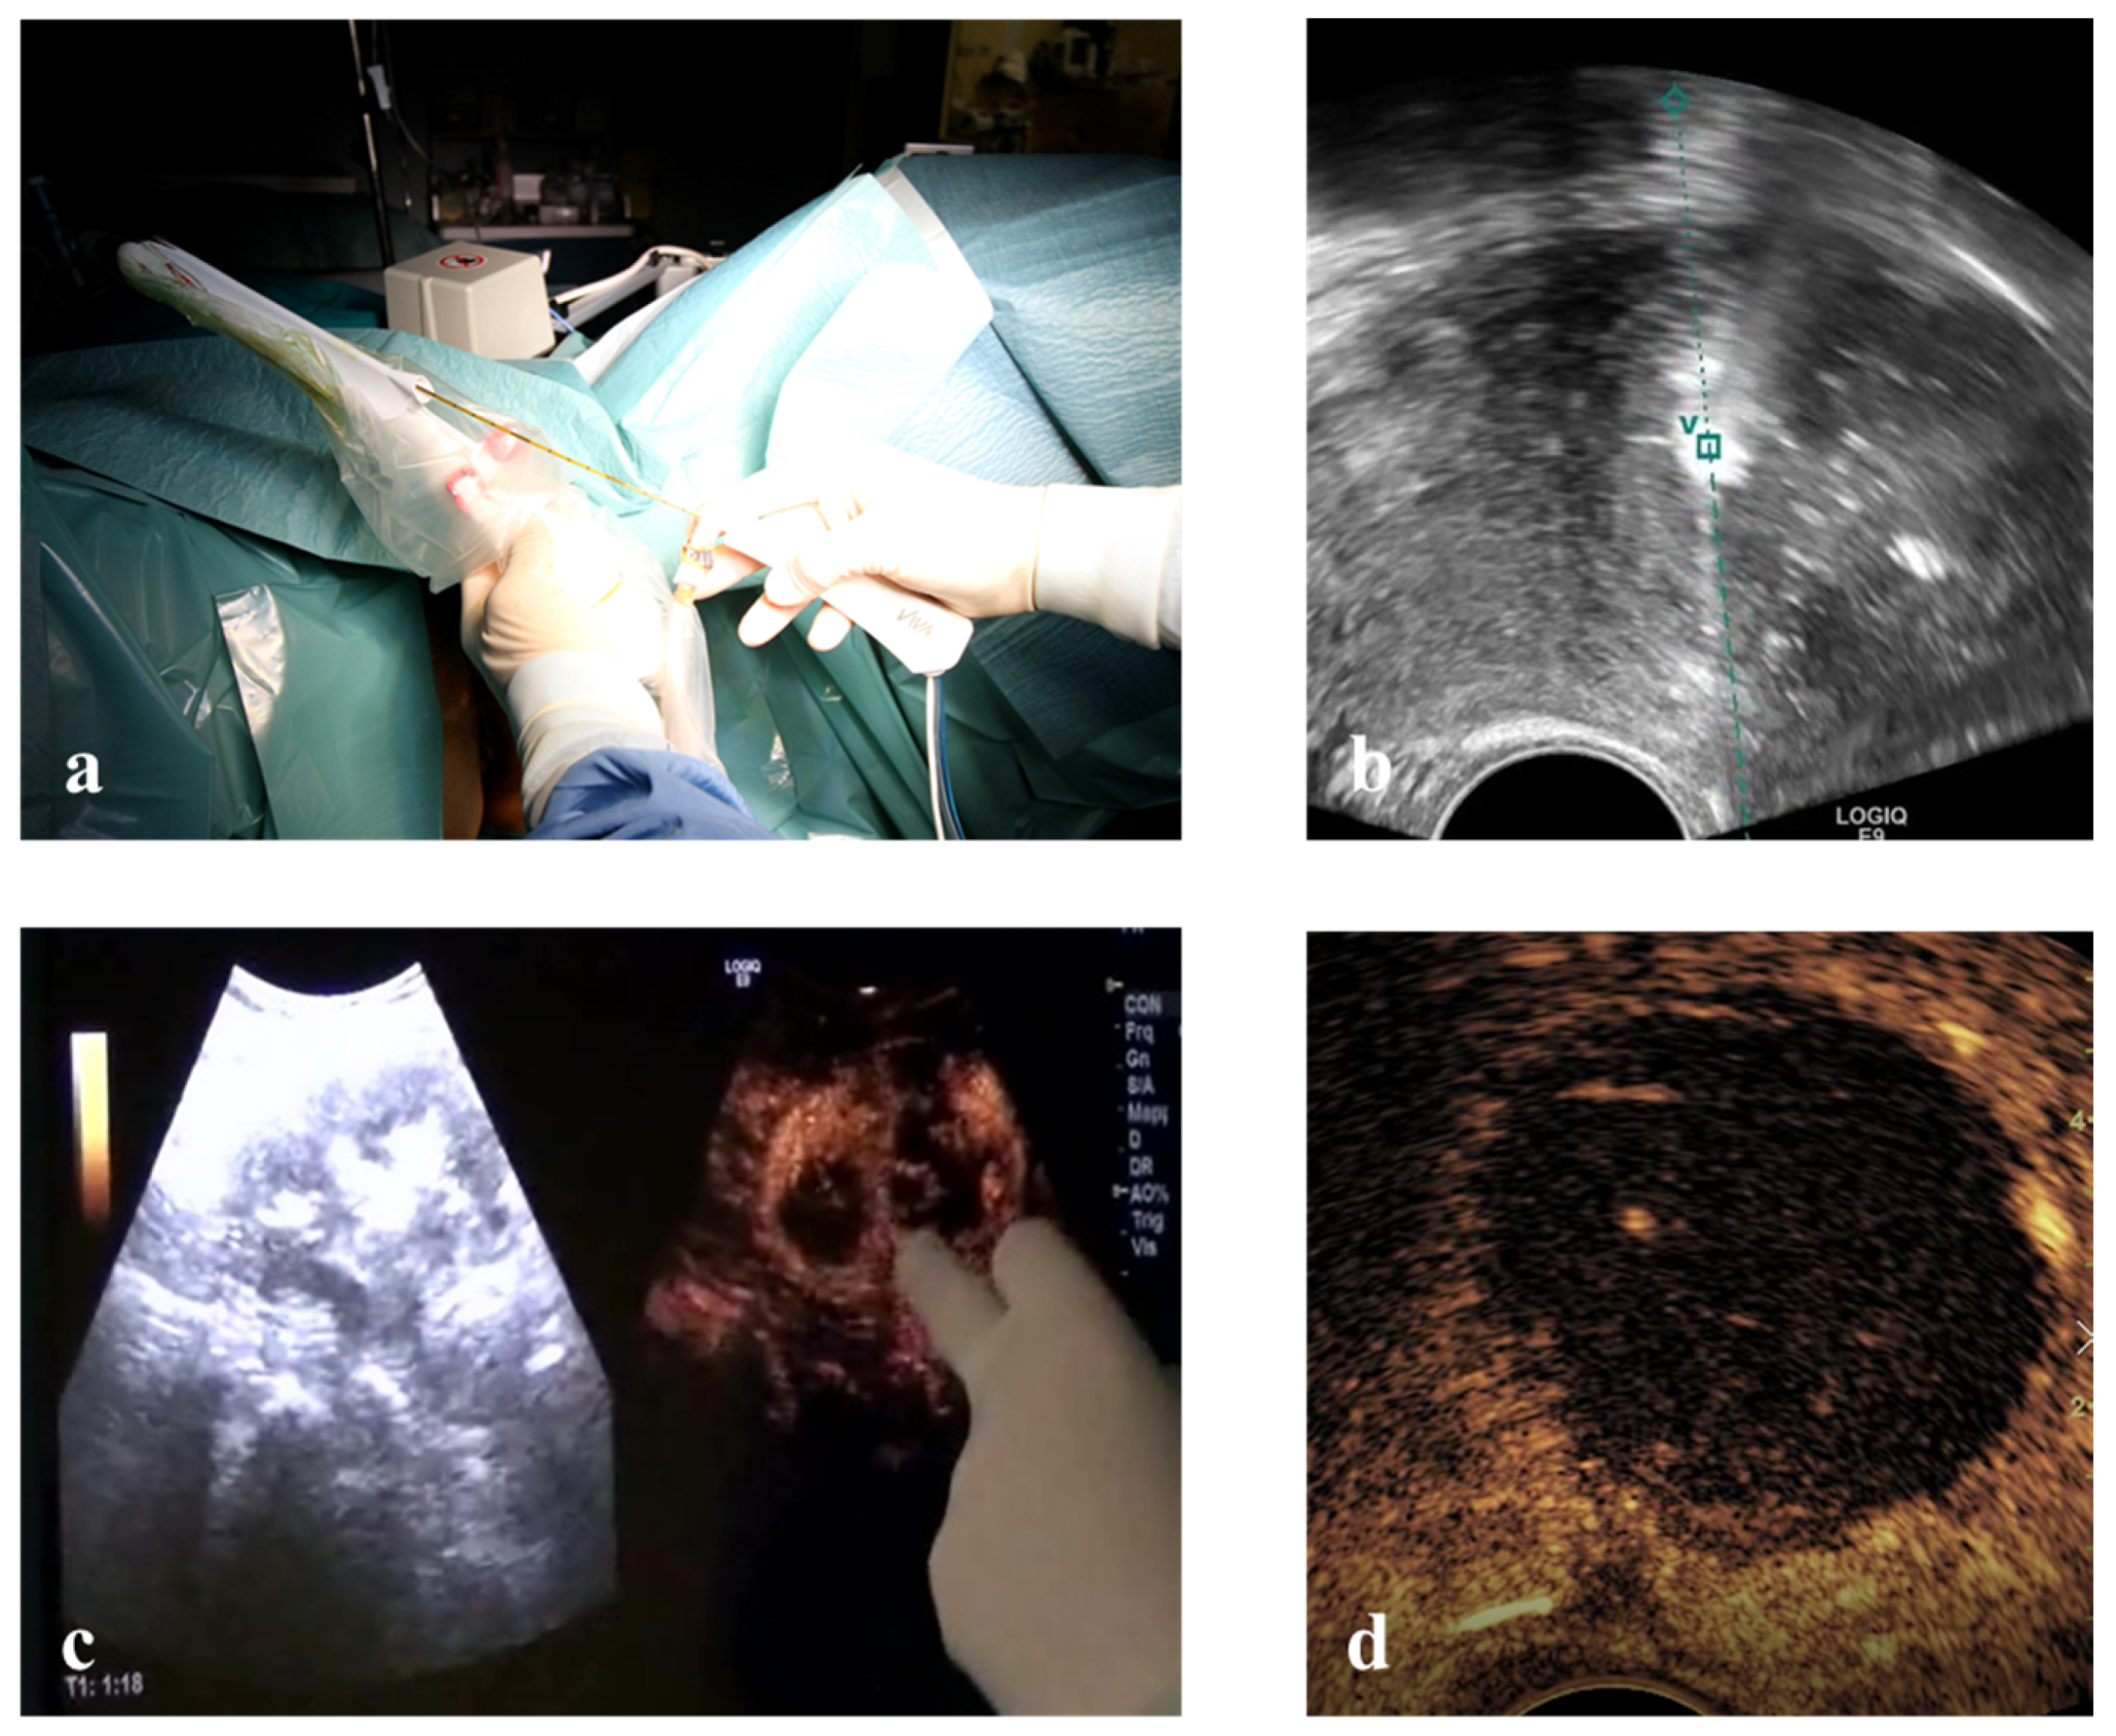

2.4. Therapy

Vaginal ultrasound-guided RFM: unconscious sedation or spinal anesthesia and dorsal position were performed on an outpatient basis after a TV ultrasound re-evaluation of the patient. Before ablation the VT track system (VirtuTRAX, CIVCO Medical Solutions, Coralville, IA, USA) was set and used together with the volume navigation system (V-Nav, LOGIQ E9, GE Healthcare, Milwaukee, WI, USA). This platform has a Global Positioning System (GPS) tracking capability to generate a 3D operating volume around the patient through the connection between three electromagnetic position sensors (2 attached to the US probe and one secured on the shaft of the RF electrode) and the position-sensing unit (Figure 2). The 10 mm active tip was then synchronized with the tracking device by a manual input of the RF electrode length, thus locating the exact position of the RF electrode and projecting its path on the US monitor during the procedure. More specifically, this system is able to guarantee an in-plane approach by displaying a green line on the B-mode when the axis of the electrode fully matches the US scan plane with the projection of the active tip marked as a square, which becomes smaller as the RF electrode approaches the image plane. From that moment onwards, the path of the RF electrode is represented by a dashed line, the prospective RF electrode path is represented by a dotted line and its active tip is located with a green V [21] (Figure 2).

Once the safest path to the target fibroid was identified both via ultrasound (TV or TA) and optically (L-RFMs and H-RFMs), the electrode was appropriately placed into the target fibroid under US real-time guidance and VT [21]. Ablation was performed with the ‘‘moving shot and stepping shot’’ technique [22], whereby the RF electrode was inserted in the distal part of the fibroid and then moved backward in steps of 5–10 s. The RF generator operated at 480 kHz with a maximum power of 200 W and at a temperature ranging from 40 to 99 °C [23]. The chosen working temperature within the fibroids was 85 °C with an automatic adjustment of the power by the device to maintain the selected temperature. Since the RF ablation time depends not only on the temperature but also on the impedance of the tissues, the tip of the electrode was cooled through a system of recirculation of cold saline solution in order to avoid the phenomenon of carbonization. Continuous US was used to monitor the procedure. The total time of ablation was determined based on increased echogenicity and continued until the echo-enhanced area reached 80–90% of the whole fibroid. At the end of ablation CEUS was performed in order to detect any eventual remaining area on enhancement (Figure 2) [21].

Figure 2. (a) Electromagnetic sensors attached to the transvaginal probe and to RF electrode connect to the low-field magnetic generator (cubic box) to provide a 3D operating volume navigation. (b) Virtual needle tracking: the path of the electrode is the dashed line and the hyper-echogenicity of RF ablation is precisely behind the active tip located with a green V. (c) Intra-operative CEUS shows residual areas within the myoma still to be treated. (d) Echo-enhanced area after a complete RF ablation of a fibroid.